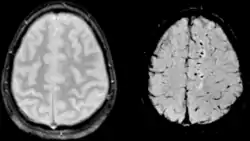

اصابة المحور العصبي يصعب اكتشافها لأنها لا تظهر بشكل جيد على الأشعة المقطعية أو مع غيرها من تقنيات التصوير العيانية على الرغم من أنها تظهر تحت المجهر. ومع ذلك، هناك الخصائص النموذجية للإصابة التي قد أو قد لا تظهر على الاشعة المقطعية. انتشار الإصابة له إصابة مجهرية أكثر من الإصابة العيانية ويصعب اكتشافه مع التصوير المقطعي و التصوير بالرنين المغناطيسي، ولكن وجودها يمكن الاستدلال عليه عندما ينزف صغيرة مرئية في الجسم الثفني أو قشرة الدماغ. التصوير بالرنين المغناطيسي هو أكثر فائدة من الاشعة للكشف عن خصائص إصابة المحور العصبي المزمن المنتشر في أطر زمنية ودون الحاد.[2] أحدث الدراسات مثل تصوير انتشار العضلة الشادة قادرة على إثبات درجة من إصابة الألياف البيضاء حتى عندما يكون مستوى التصوير بالرنين المغناطيسي هو سلبي. بما ان تضرر المحور العصبي يكون إلى حد كبير نتيجة البيوكيميائية الثانوية لأن لديها تأخر، لذلك الشخص مع الإصابة ي يبدو في البداية بشكل جيد قد تتدهور حالته في وقت لاحق. وبالتالي الإصابة في كثير من الأحيان أشد من أن تدرك، و المهن الطبية ينبغي أن تشتبه في اصابة أي من المرضى الذين تظهرهم الأشعة المقطعية العادية ولكن لديهم اعراض مثل فقدان الوعي.

التصوير بالرنين المغناطيسي هو أكثر حساسية من المقطعية ولكن التصوير بالرنين المغناطيسي قد لا يرى أيضا الإصابة، لأنه يحدد الإصابة به علامات والتي قد لا تكون موجودة.